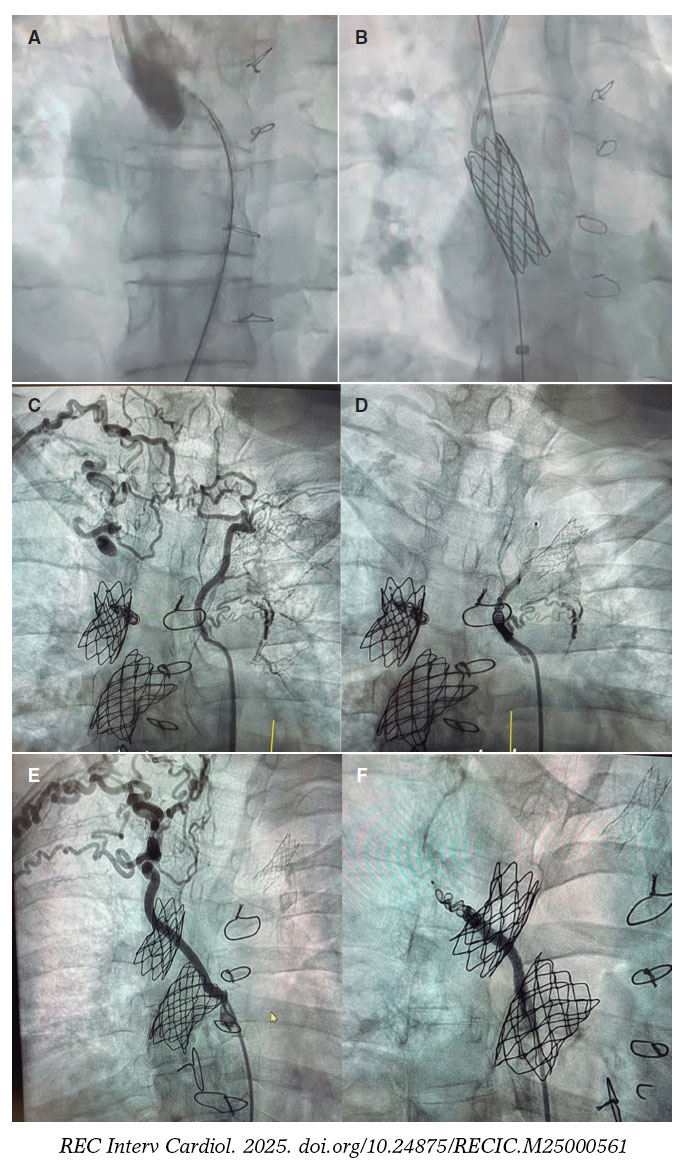

En nuestro medio, la experiencia desde 2015 de trabajo conjunto entre equipos pediátricos y de adultos ilustra bien esta filosofía. No se trata de compartir la sala de hemodinámica, sino de generar espacios comunes de discusión y decisión, en sesiones clínicas multidisciplinarias que permitan unificar criterios y diseñar estrategias personalizadas. Un buen ejemplo reciente, que refleja los beneficios de este trabajo conjunto, es un caso de optimización de Fontan con implante de stents y cierre de colaterales. La paciente, de 41 años, atendida en nuestro centro, presentaba una cardiopatía congénita compleja con corazón univentricular, concordancia auriculoventricular y discordancia ventriculoarterial, transposición completa de las grandes arterias, comunicación interventricular amplia, estenosis pulmonar e hipoplasia de ventrículo derecho. Se había sometido a numerosas cirugías y procedimientos previos (fístula de Blalock-Taussig a los 13 meses de edad, fístula sistémico-pulmonar a los 2 años y medio, derivación cavopulmonar superior tipo Glenn bidireccional a los 9 años, y derivación cavopulmonar inferior tipo Fontan extracardiaco a los 17 años), y presentaba una capacidad funcional disminuida y hepatopatía asociada al Fontan. Se le realizó un cateterismo cardiaco que confirmó la presencia de un tubo de Fontan muy calcificado y con una importante estenosis en su inserción a la rama pulmonar derecha. Inicialmente se procedió al tallaje con balón y luego al implante de un stent recubierto posdilatado con balón de 20 mm, con buen resultado. Por vía venosa yugular se confirmó una estenosis marcada en la anastomosis del Glenn a la rama derecha y se procedió al implante de un stent desnudo de 34 mm (figura 1A-B). Por vía arterial se realizó una aortografía en la que se observaron gruesas colaterales a ambos campos pulmonares, y se procedió a su cierre. La primera, hacia el lóbulo pulmonar superior derecho e izquierdo con tapón Amplatzer Vascular Plug 4 (Abbott Cardiovascular, Estados Unidos) y coils; la segunda, hacia el lóbulo superior derecho con tapón Amplatzer Vascular Plug 4 y coils (figura 1C-F). Este caso refleja muy bien la sinergia entre los hemodinamistas pediátricos y de adultos para completar el tratamiento.

Figura 1. Optimización de Fontan. A: estenosis en la anastomosis del Glenn con la rama derecha. B: stent desnudo implantado en dicha estenosis. C: gruesa colateral aortopulmonar que va hacia los lóbulos pulmonares superiores derecho e izquierdo. D: cierre de dicha colateral. E: gruesa colateral aortopulmonar que va hacia el lóbulo superior derecho. F: cierre de la colateral.